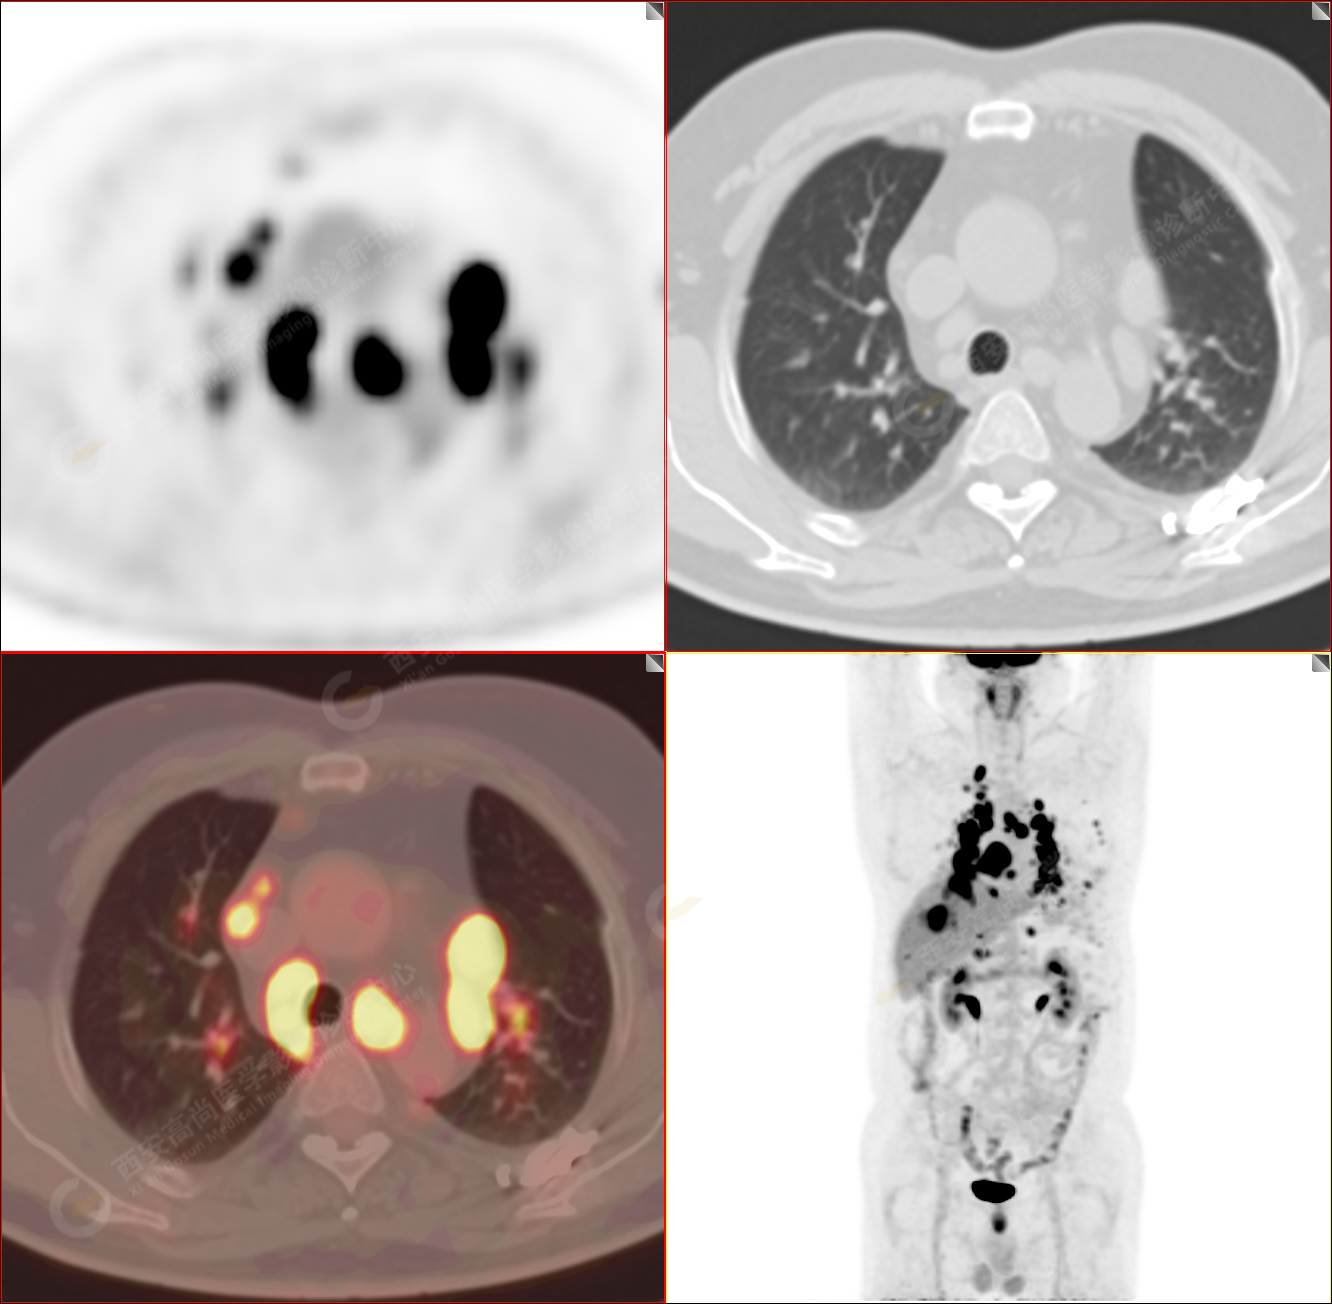

PET/CT-MR診斷結(jié)節(jié)病雙肺及全身多發(fā)淋巴結(jié)廣泛累及1例【西安高尚病例】

男性,53歲,頭暈半月入院,CT發(fā)現(xiàn)肺內(nèi)腫塊,雙肺多發(fā)大小不等實(shí)性及粟粒樣結(jié)節(jié),雙肺門(mén)及縱隔多發(fā)腫大淋巴結(jié)。病程中無(wú)發(fā)熱、胸悶氣及胸部不適。既往:左側(cè)肋骨外傷史。

PET/CT圖像

PET-MR圖像